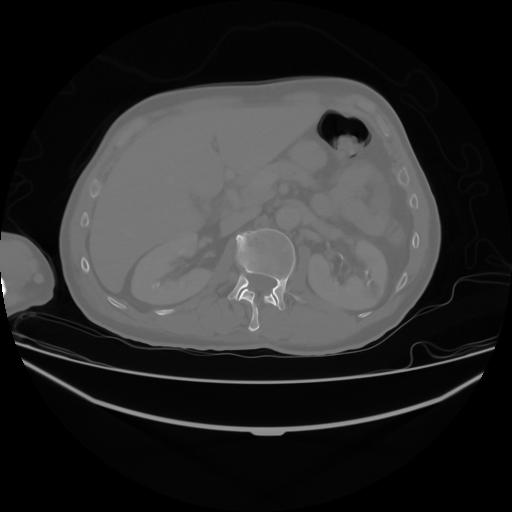

4 CUERPO,CE,Axial,3.0,CUERPO,,